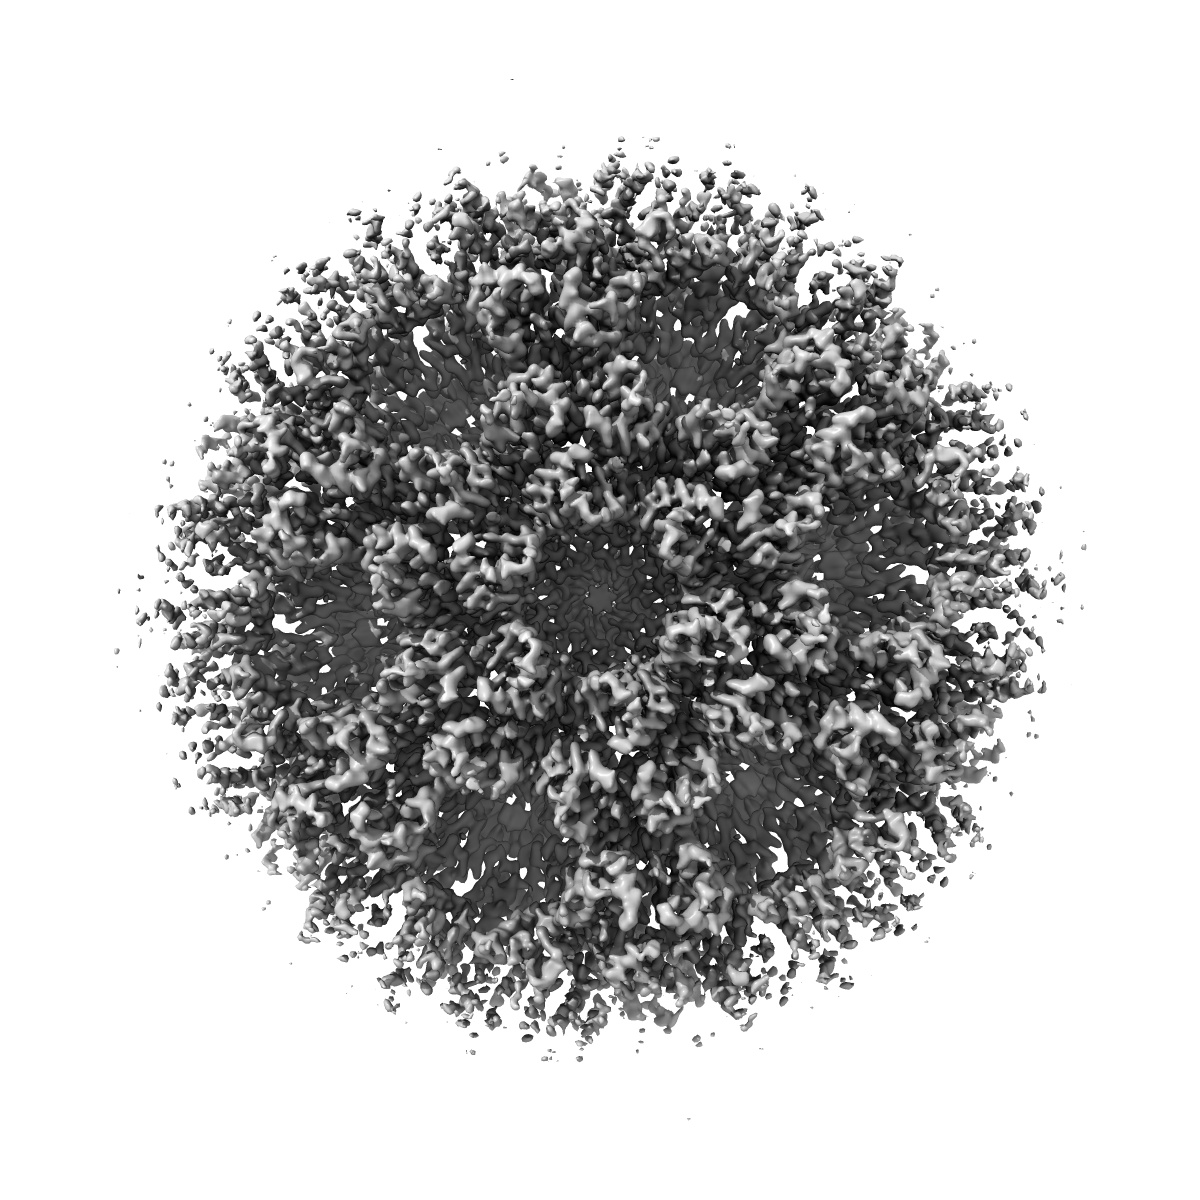

Gag CA-SP1 immature lattice bound with Lenacapavir from enveloped virus like particles (T8I)

Single-particle

3.13 Å

Structural insights into inhibitor mechanisms on immature HIV-1 Gag lattice revealed by high-resolution in situ single-particle cryo-EM.